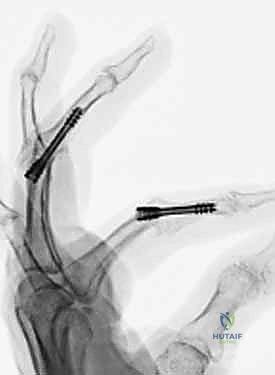

Figure 1: Recommended positions for digital joint fusion.